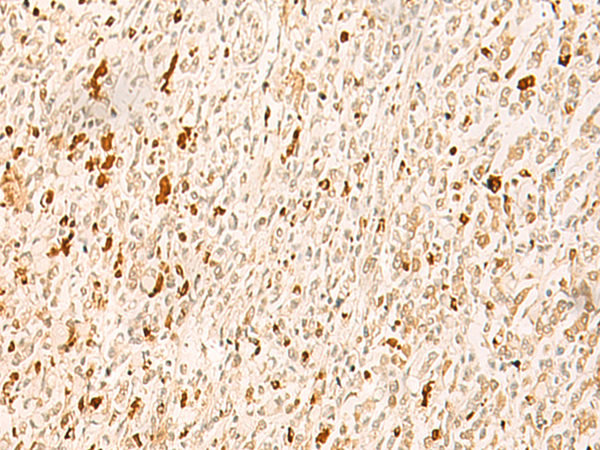

分类: 科研抗体货号: P02990别名: HSPC210; C14orf129应用: IHC反应种属: Human, Mouse, Rat